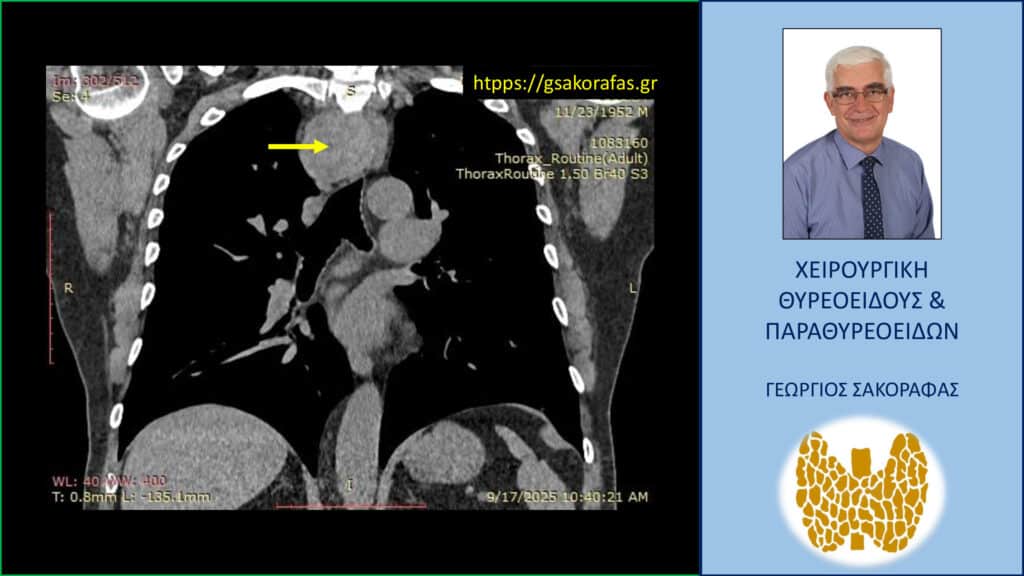

- Γιατί είμαστε σε θέση να εκτελέσουμε με ασφάλεια και αποτελεσματικότητα κάθε είδους χειρουργική επέμβαση θυρεοειδούς – παραθυρεοειδών, ακόμη και σε επιπλεγμένα (δύσκολα) περιστατικά, όπως εκτεταμένοι λεμφαδενικοί καθαρισμοί σε καρκίνο θυρεοειδούς, επεμβάσεις σε λίαν ευμεγέθεις καταδυόμενες στο μεσοθωράκιο βρογχοκήλες, υποτροπές παθήσεων θυρεοειδούς (συμπεριλαμβανομένου του καρκίνου θυρεοειδούς), υποτροπές υπερπαραθυρεοειδισμού, αδενώματα παραθυρεοειδών σε έκτοπη θέση ή λόγω υπεράριθμων παραθυρεοειδών, διάχυτη υπερπλασία παραθυρεοειδών, κλπ.